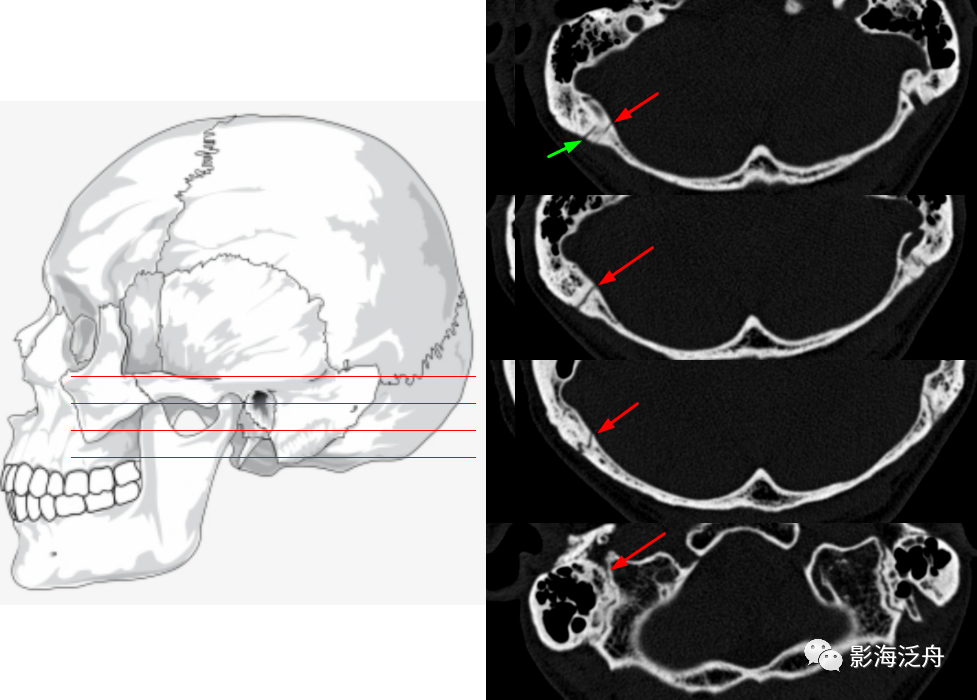

右侧颧弓骨折(红箭),注意对照前文的解剖标注图里的标注区2,颞骨与